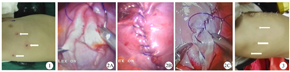

麻醉满意后患儿取健侧卧位,头高足低,无需单肺通气。主刀及助手站位于患儿头侧,监视器位于足侧。于第六肋间腋中线取0.5 cm皮肤切口为观察孔,于第四肋间腋前线、第六肋间肩胛下角线分别取0.5 cm操作孔(图1)。置入5 mm的Trocar建立人工气胸4~8 mmHg(1 mmHg=0.133 kPa),置入胸腔镜观察,调整气胸压力至膈面位于基本平直的水平,并置入器械。膈肌折叠缝合方向为侧胸壁肋膈角至心膈角。选用2-0带双针的可吸收双向倒刺线,先将1枚缝针于肋膈角处经皮肤刺入胸腔。开始膈肌折叠,缝针的进、出针均位于薄弱膈肌边缘外侧的正常膈肌,膈肌麻痹患儿则缝合在适当的部位,将薄弱或麻痹的膈肌折向腹腔。第一针缝合拔针抽线至缝线的中点(正、反向倒刺交界区,1/2线长处),胸壁外的缝线用纱布包裹2层后用血管钳固定,起悬吊固定的作用。连续缝合,抽紧缝线,折叠膈肌至心膈角(图2A),末端重叠缝合2针,剪断缝线。然后将手术床放平,去除气胸压力,即刻评估手术的效果。如果膈肌下降满意,即膈顶不高于心膈角,则将胸壁表面的缝线提起,剪断缝线,完成膈肌折叠(图2B)。如果膈肌下降不够满意,即膈顶高于心膈角,则将另外半截缝线及缝针拉入胸腔,由肋膈角开始,再次连续缝合并进一步折叠膈肌至心膈角,剪断缝线(图2C)。拆除Trocar,可以经观察孔选择是否安置引流管。

32例患儿的手术时长为(83.0±29.5)min,范围25~165 min;术中出血量为(3.0±3.6)ml,范围0~10 ml(中位出血量为2 ml);除5例患儿术后未安放胸腔引流管外,余均安放引流管,术后胸腔引流管置管天数为(5.89±3.36)d,范围0~14 d;术后引流量为(161±148)ml,范围0~600 ml(中位引流量为115 ml)。所有患儿均未输血。术后住院时间为(10.1±3.5)d,范围6~19 d。术后患儿均进行面部表情疼痛评分法,疼痛评分为(0.3±0.6)分,范围0~2分;所有患儿于术后1周内拍摄胸部正、侧位X线片,显示膈肌下降(2.2±0.9)个肋间,范围1~4个肋间。患儿出院后1个月、6个月、1年和3年进行门诊随访。患儿出院后均获得随访,随访时间为(20.6±8.2)个月,范围12~36个月,患儿呼吸道症状均不同程度缓解或消失,随访期间无手术相关并发症发生和膈膨升复发。门诊复查见患儿手术部位瘢痕小,具有良好的美容效果(图3)。